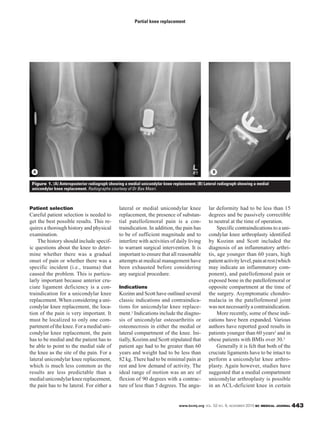

Figure 1. (A) Anteroposterior radiograph showing a medial unicondylar knee replacement. (B) Lateral radiograph showing a medial

unicondylar knee replacement. Radiographs courtesy of Dr Bas Masri.

A unicondylar knee replacement

( ) consists of a metal compo-Figure 1

nent that goes on the femoral condyle,

and another component that goes on

the tibial side. The tibial component

can be metal-backed with a fixed-

bearing or mobile-bearing polyethyl-

ene bearing surface, or it can be an all-

polyethylene fixed-bearing cemented

component. There is no evidence that

one approach is better than another.